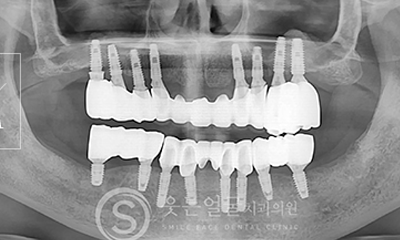

한눈에 보는

임플란트 전후사진